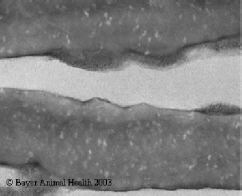

- White spots or bands in the mucosa. In severe infections they become confluent and cause sloughing of the mucosa.

- A system of assessing the severity of coccidial challenge by attributing a 'score' is often used. A detailed description is beyond the scope of this book. In general terms a score of 0 indicates no lesions and a score of 4 indicates maximal severity of lesion or death. Various publications provide a photographic key to severity of lesion.

| Figure 12. Moderate Eimeria acervulina infection (score 2) in chicken duodenum. In milder infections there may be scattered white spots, in severe the entire surface is pale or denuded of epithelium. |